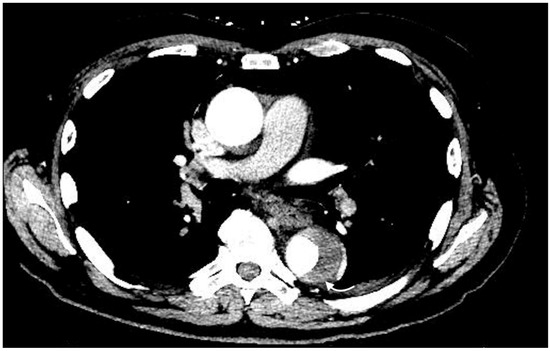

2.4.1. Active Arterial Extravasation